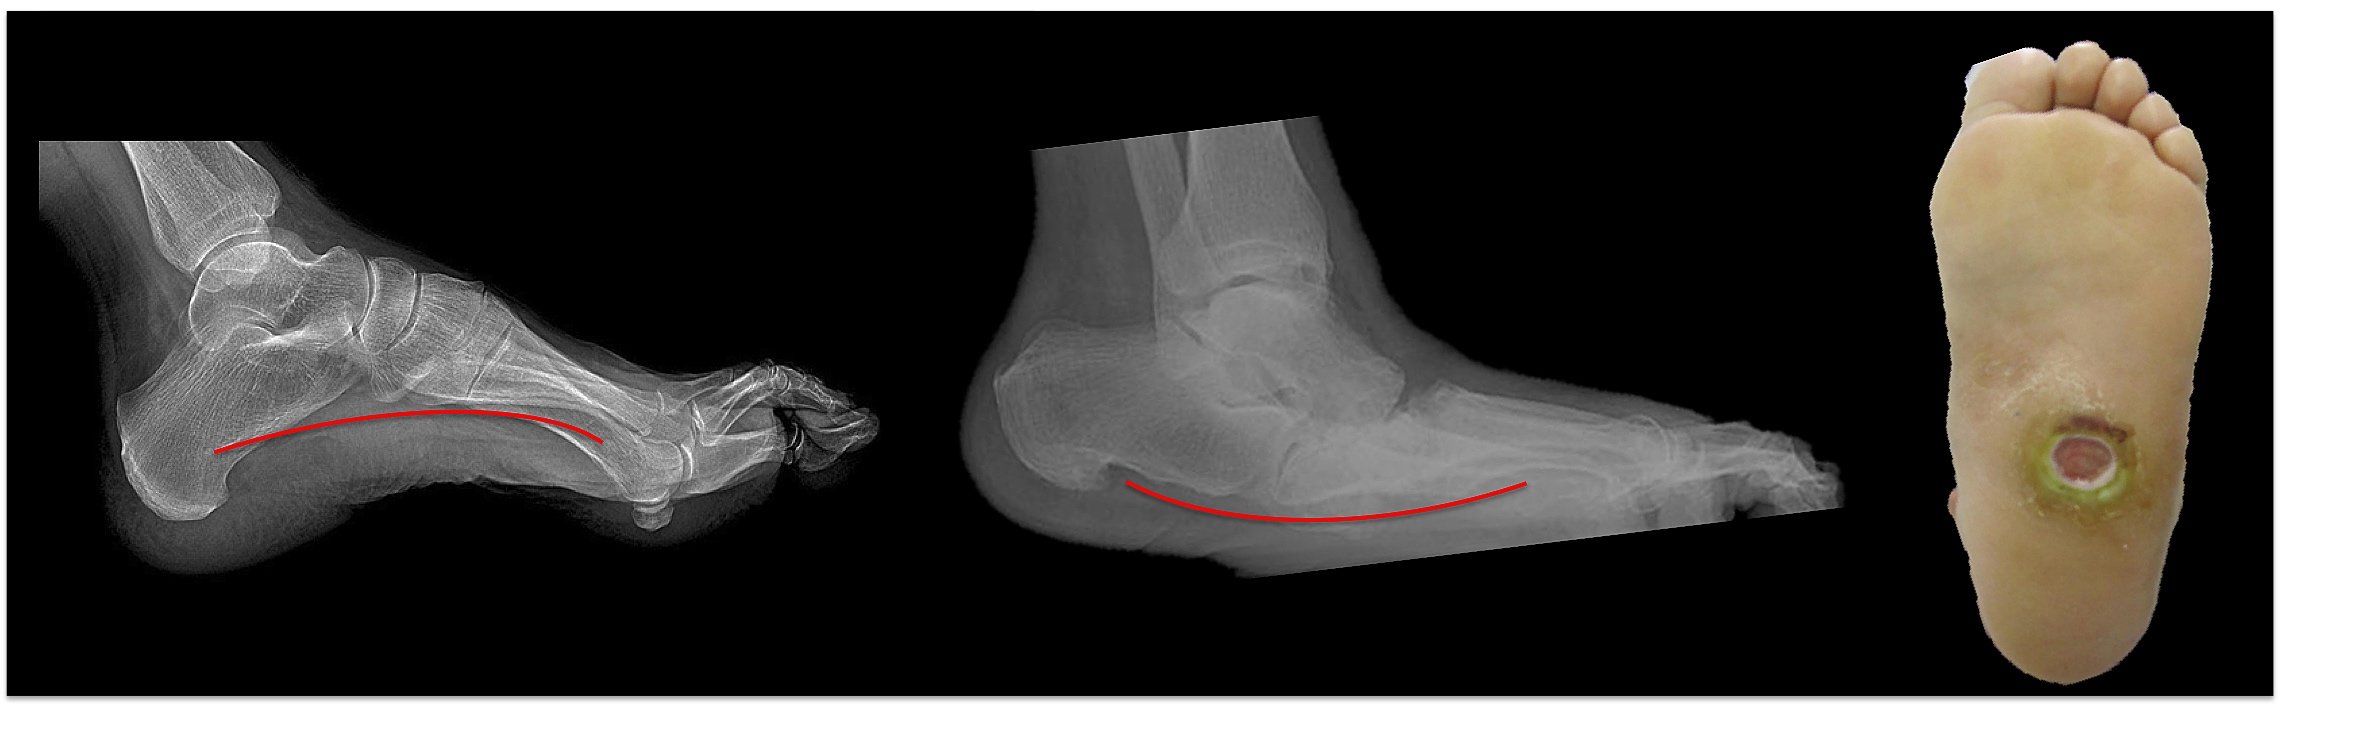

The picture below shows what is known as a rockerbottom charcot deformity of foot. in xray on left the arch is normal, in the charcot patient xray in middle you can see the red line showing arch that has collapsed creating a rockerbottom appearance to the foot. This is dangerous because in the face of neuropathy ( skin numbness- which is common in diabetes ) the patient can develop a wound ; we call an ulceration in that area where the bump is prominent as pictured in the rightmost image.

This can occur even if immediate correct treatment is enacted since the deforming forces of the tendons and ligaments are so strong in the limbs. The acute phase of the charcot process is called the inflammatory phase and can last from several weeks to months. When the redness, warmth and edema subside this marks the second phase which is called the ossification phase where the patients own body tries to mend the bones together. If there is enough bone mass the body can be successful in healing the foot unfortunately in the foot has become deformed during the acute first stage the body will heal the foot in an abnormal position. This is the rocker bottom foot position which then allows the midfoot prominence of bone to quickly break down the skin and cause a diabetic foot ulcer. This can lead to limb loss in the most severe of cases. The final stage of the charcot process is the remodeling phase. Here the patients own body attempts to recreate as much of the normal foot architecture as possible through absorbing bone where it should not be and creating bone in areas it should be.